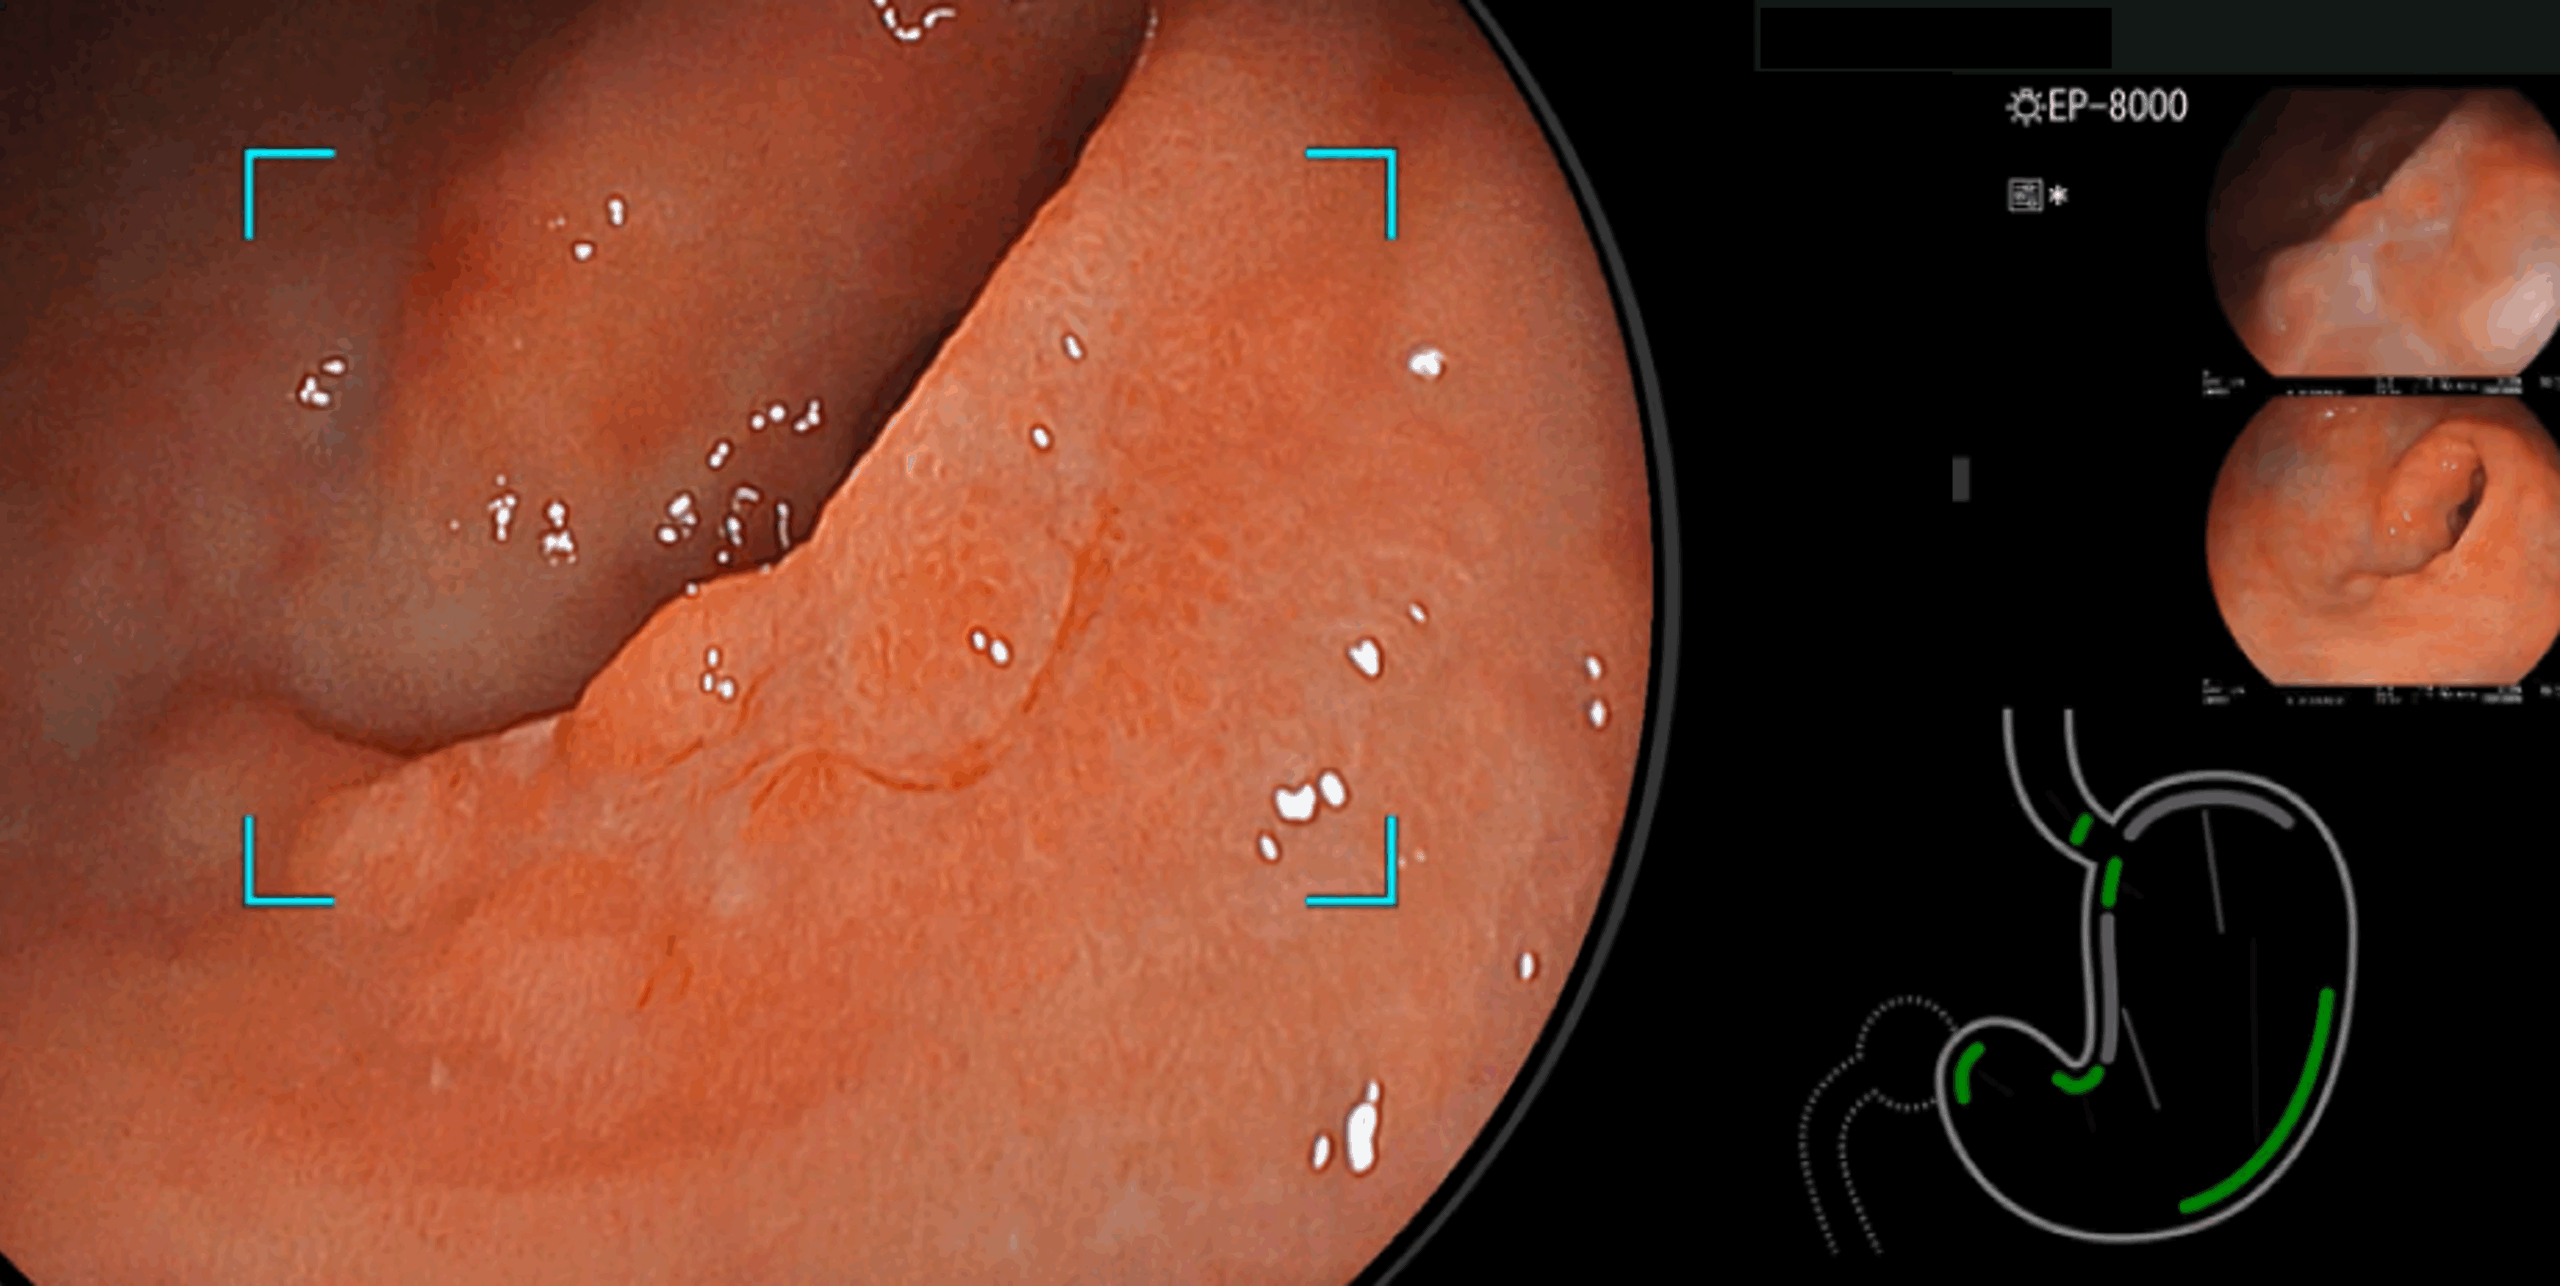

内視鏡AI2025/11/21人工知能を用いた早期胃癌拡大内視鏡診断支援システムの性能評価【期間限定オンデマンド配信】